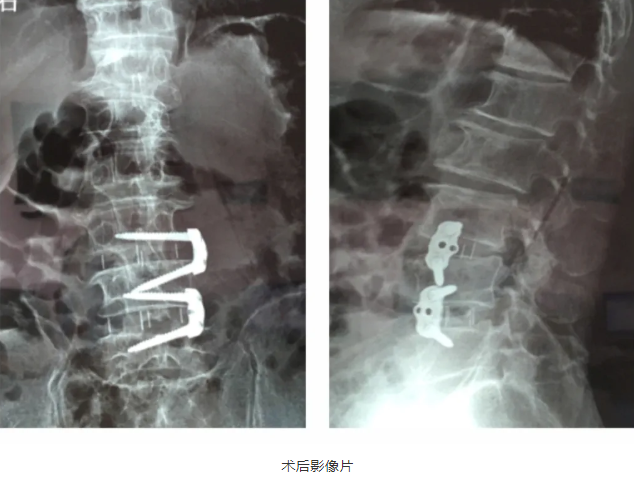

2021年7月2日-4日,中国医师协会第三届显微外科医师年会在宁波举行。我院医疗院长桃春辉当选本届全国委员,会上代表医院报告我院开展的显微镜下脊柱微创OLIF技术,受到了与会专家们关注。

“OLIF作为一种更加微创的椎间融合术,近几年在国内各大医院逐渐开展,获得越来越多临床医生的认可”桃春辉院长介绍,该手术经左下腹腹外斜肌、腹内斜肌、腹横肌的肌间隙进入腹膜外间隙,在左侧腰大肌和腹主动脉之间安放工作通道,可通过大血管间隙及腰大肌间入路进行手术,可明显减少手术创伤、缩短手术时间、减少术中出血、缩短住院时间及患者康复时间。